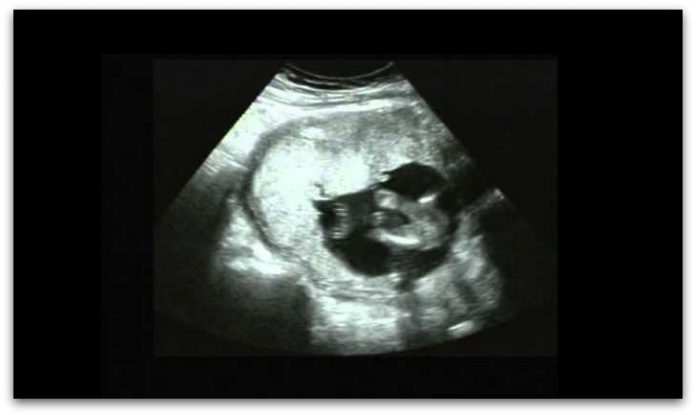

Видеото што можете да видите тука покажува како пар кој има секс е снимен во 4D ултразвук, а авторот Мери Роуч раскажува како се согласила да учествува во овој потфат.